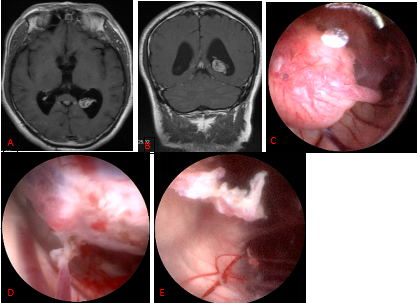

1. 垂体瘤

目前,绝大多数垂体瘤首选内镜经鼻手术治疗。

图1. A-C 向蝶鞍下方发展的侵袭骨质的垂体腺瘤。A、C 术前、术后轴位T1增强MRI。B术中所见,向侧下方磨除被肿瘤侵袭的颈静脉结节骨质。D-L 广泛侵袭颅底的垂体腺瘤。D、F术前、术后1年矢状位T1增强MRI。E 术中骨窗显露范围。G 肿瘤切除后正常垂体予以保留。H 肿瘤切除后第三脑室开放。I肿瘤切除后显露额叶及前交通动脉复合体。K 斜坡后方肿瘤切除后显露脑干及桥前池。J、L术前、术后1年冠状位T1增强MRI。1斜坡;2右侧视神经管;3视神经管-颈内动脉隐窝;4蝶骨平台硬膜;5鞍结节硬膜;6 鞍底硬膜;7斜坡硬膜;8 斜坡旁段颈内动脉;9第三脑室;10 垂体柄;11额叶直回;12 前交通动脉复合体;13脑干;14基底动脉;15左侧外展神经。黄色箭头所示为被肿瘤侵袭的颈静脉结节;无尾黄色箭头所示为正常垂体。